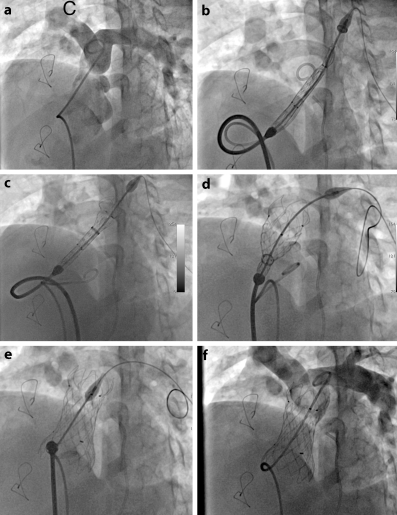

Fig. 4

Fluoroscopic images demonstrating several steps of the implantation procedure. Basal angiogram in the main pulmonary artery in LAO and cranial projection to visualise pulmonary artery bifurcation (a), advancing and positioning Venus p‑valve delivery system in the RVOT with the tip advanced into proximal left branch (b), deployment of the distal end of the valve (c), deployment of the central part of the valve (d), Venus p‑valve completely deployed in an appropriate position (e) and final angiogram demonstrating a functional valve and patent pulmonary branches (f)